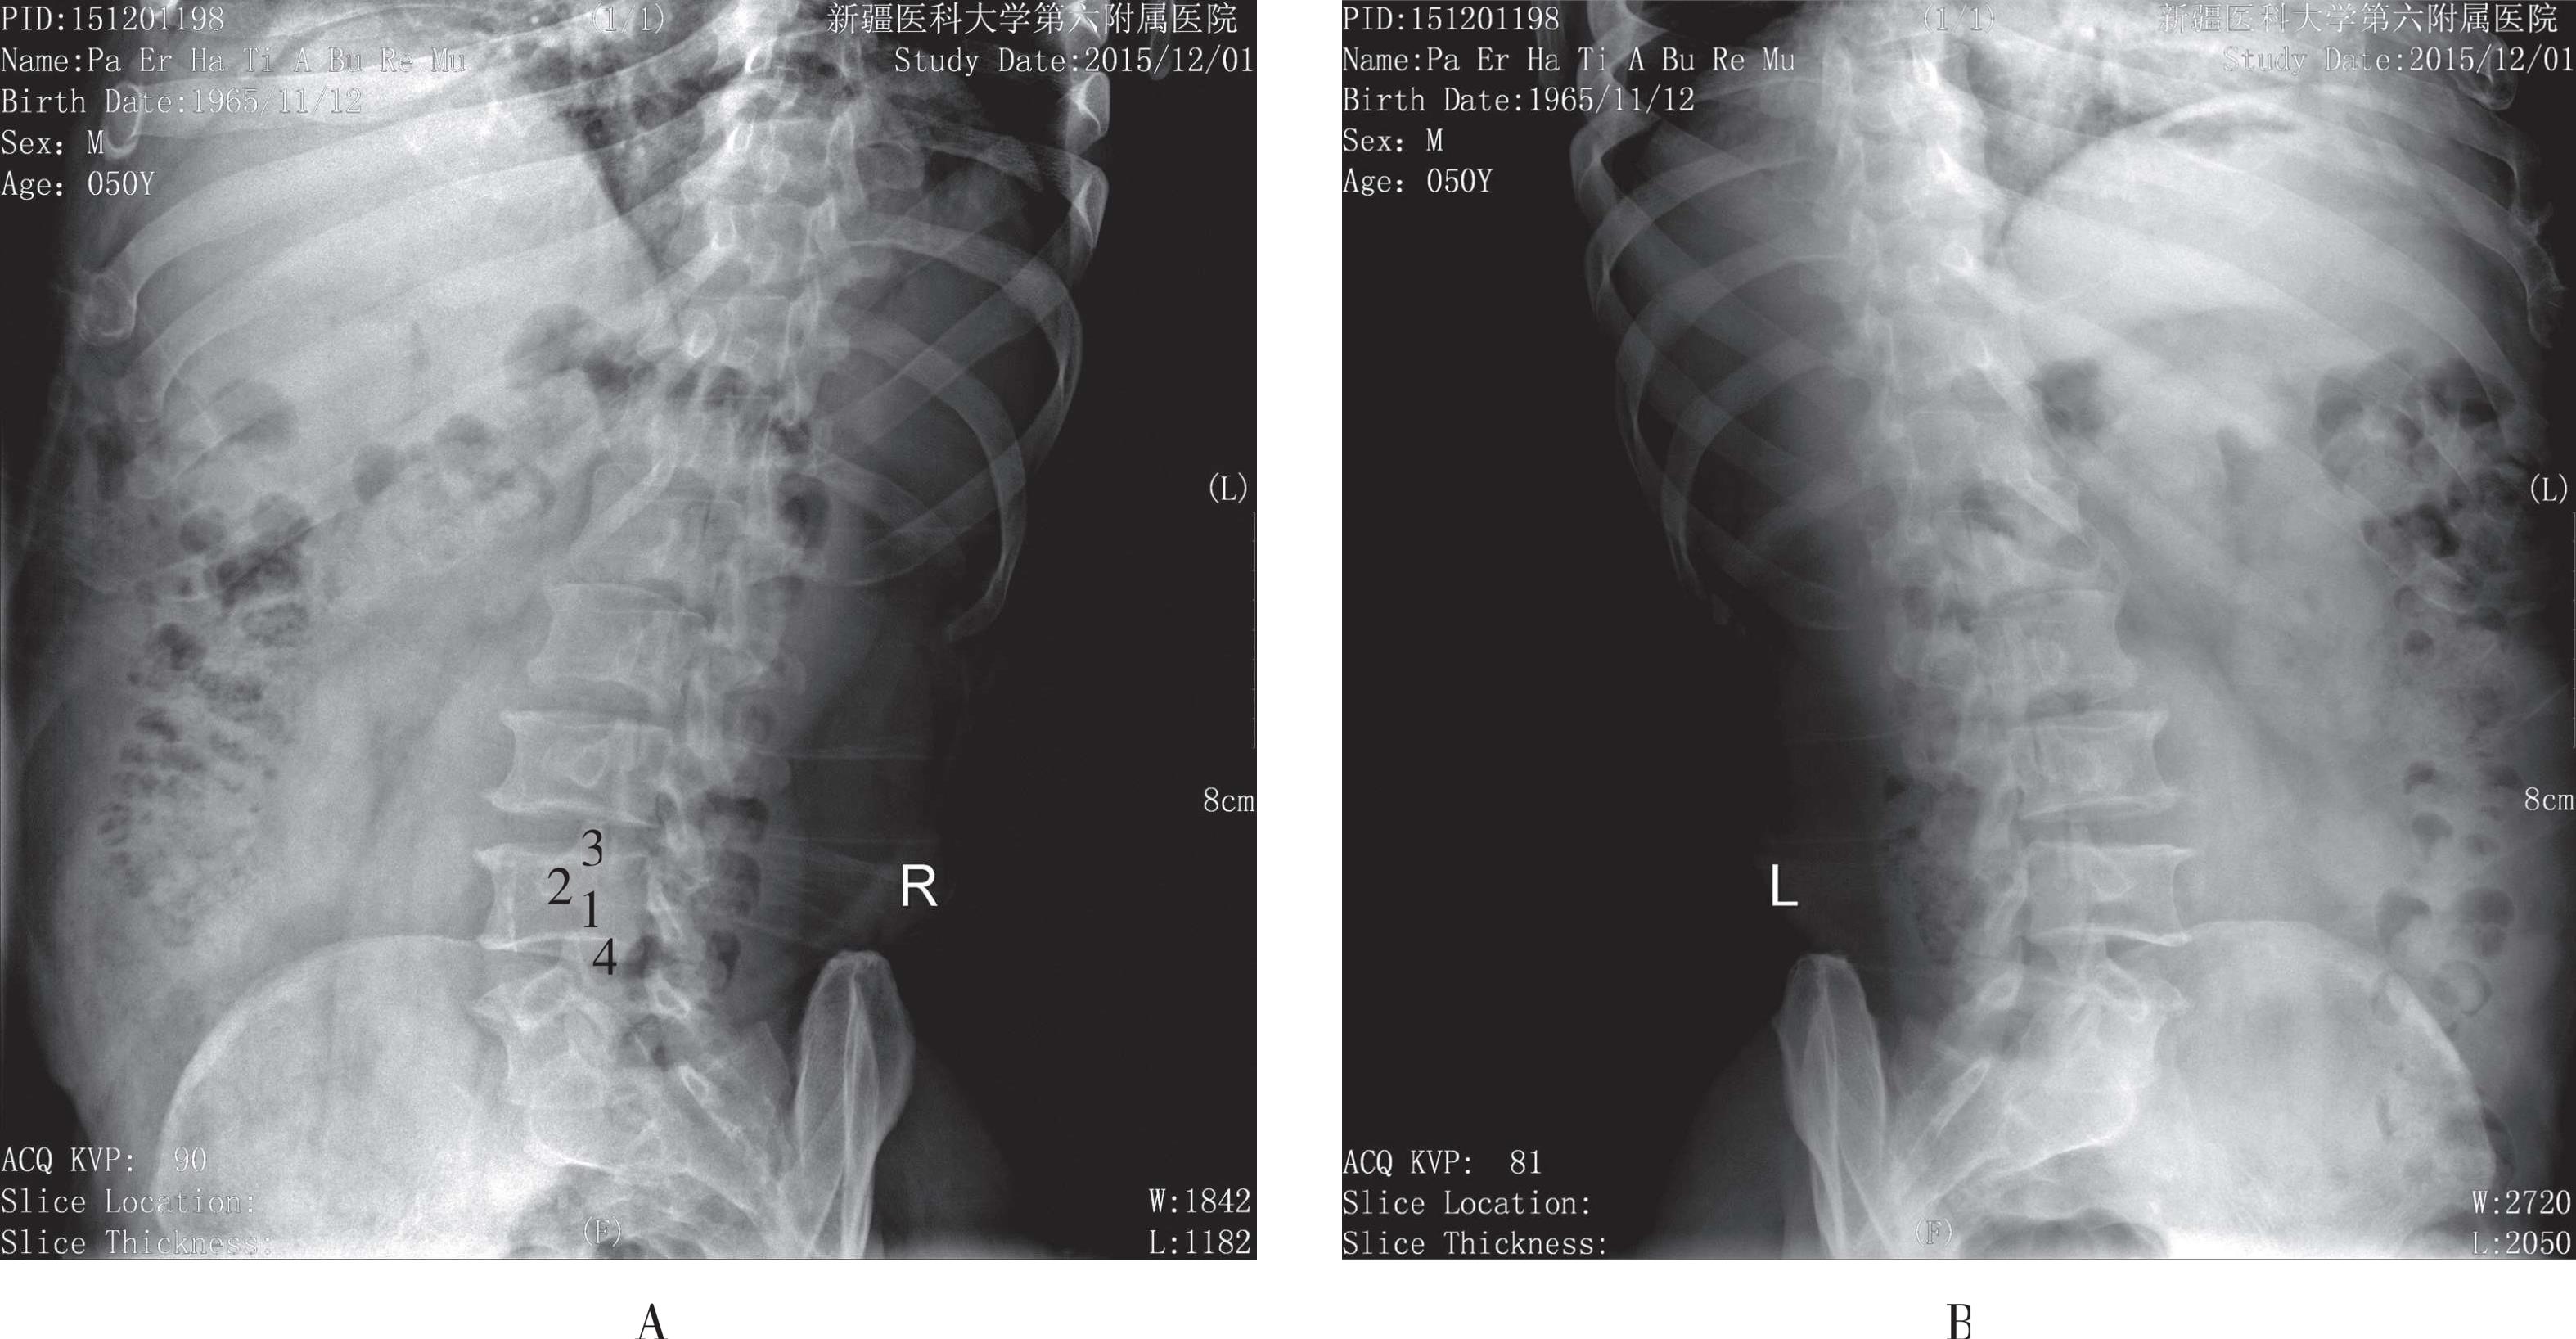

被检者仰卧于检查床上,身体正中矢状面对准检查床的中线,双下肢屈曲,双足踏于床面,使腰背部尽量贴近床面,两臂置于身旁或上举,影像接收器上缘包括T 11 ,下缘包括上部骶椎,两侧包括腰大肌,中心线对准L 3 (相当于脐上3cm处)垂直射入。影像显示T 11 ~S 2 的椎骨及两侧腰大肌,腰椎椎体为两侧稍凹的四方形,椎间隙显示清晰,两侧横突对称,L 3 横突较长,椎弓根、椎间关节、棘突亦显示清晰,各椎体骨小梁显示清晰,腰大肌及周围软组织层次可见(图3-13)。

1. L 1 椎体;2. L 3 椎体横突;3. 椎板;4. 棘突

图3-13 腰椎正位片

1. 椎体;2. 椎间隙;3. 棘突;4. 下关节突;5. 上关节突

图3-14 腰椎侧位片